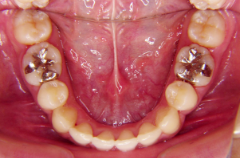

装置装着前